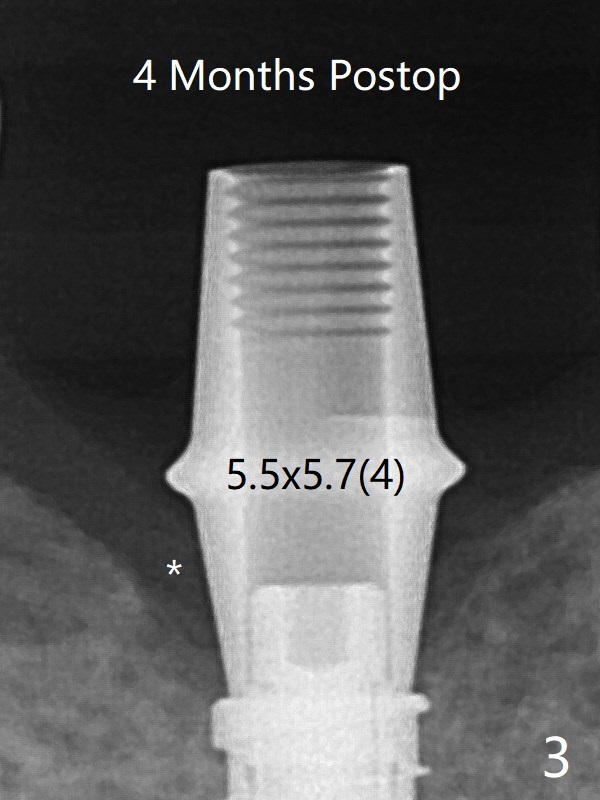

There is crestal bone loss 4 months postop (Fig.3,4).  It appears that the implant was placed excessively deep.